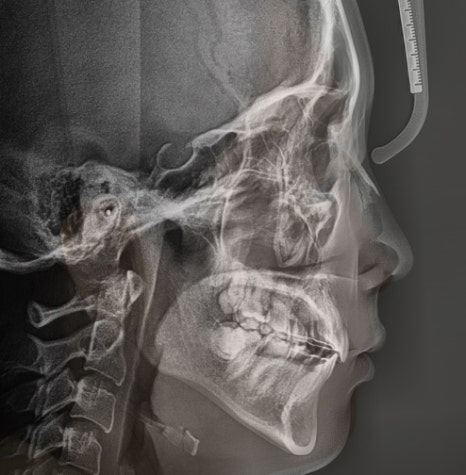

부정교합 2급 이라는 것은, 하악보다 상악이 더 전방에 위치되거나 또는 상악의 치아들이, 하악 치아들보다 더 앞쪽에 위치되어 있는것을 뜻하며

증세를 갖고 계셨던 분의 임상 증례를 보여드립니다. 교정 치료를 통해서 2급 부정교합이 개선 되었으며 치료를 끝으로, 턱 끝에 보형물